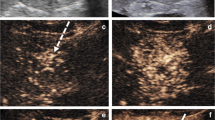

Image data captured at maximum tumor diameter were saved in JPEG format on a personal computer and analyzed using ImageJ version 1.47 software (National Institutes of Health, available at http://rsb.info.nih.gov/ij). Outlines of hepatic nodules were drawn free-hand by three hepatologists who were board-certified Fellows of the Japan Society of Ultrasonics in Medicine (FJSUM), and analyzed in “ROI Manager” mode. Analyzed values were circularity, solidity, aspect ratio, median gray value, mean gray value, modal gray value, minimum gray value, maximum gray value, and standard deviation of gray value. These parameters were automatically calculated using ImageJ software. Each analyzed value was defined as follows (Figs. 1, 2) [12].

Outliers were detected for standard deviation of HCC, median gray value and solidity of liver metastasis, and median gray value of hemangioma. Other data were not detected as outliers (Fig. 3). Mean values for HCC were as follows: aspect ratio 1.237 (range 1.161–1.297); circularity 0.895 (range 0.823–0.939); solidity 0.975 (range 0.954–0.982); minimum gray value 18 (range 18–21); maximum gray value 144 (range 144–144); median gray value 65 (range 63–66); mean gray value 66.3 (range 65.2–67.5); modal gray value 60 (range 60–71); and standard deviation of gray value 22.8 (range 22.3–23.0).

Mean values for hemangioma were as follows: aspect ratio 1.203 (range 1.143–1.266); circularity 0.820 (0.754–0.875); solidity 0.960 (0.926–0.977); minimum gray value 14 (12–14); maximum gray value 173 (153–207); median gray value 68 (67–70); mean gray value 69.1 (67.8–70.4); modal gray value 71 (71–71); and standard deviation of gray value 20.9 (18.4–21.2).

Mean values for liver metastasis were as follows: aspect ratio 1.849 (range 1.667–1.992); circularity 0.745 (0.680–0.784); solidity 0.947 (0.920–0.963); minimum gray value 5 (5–6); maximum gray value 130 (111–156); median gray value 47 (43–49); mean gray value 49.2 (45.4–51.6); modal gray value 43 (43–43); and standard deviation of gray value 19.8 (17.0–21.6).